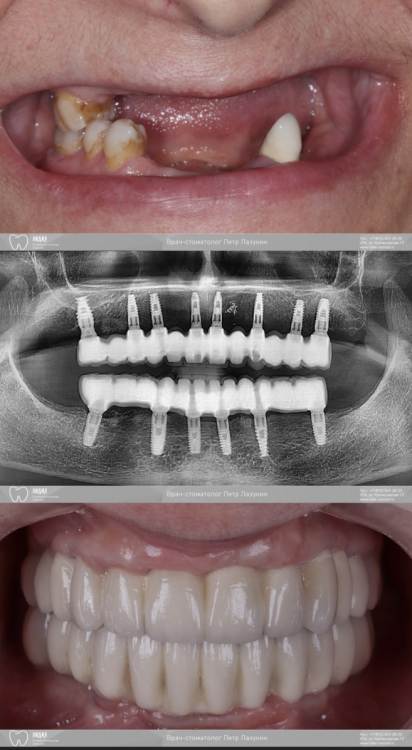

pit Опубликовано 29 ноября, 2021 Поделиться Опубликовано 29 ноября, 2021 (изменено) Планировал верх сделать из 4х сегментов, но не смог установить имплант в позицию 24 зуба- сломал гребень. Решил сделать в/ч подковой. Видео имплантации на н/челюсти здесь: https://youtu.be/T2__zlmJEm8 Изменено 29 ноября, 2021 пользователем pit 8 1 2 Ссылка на комментарий